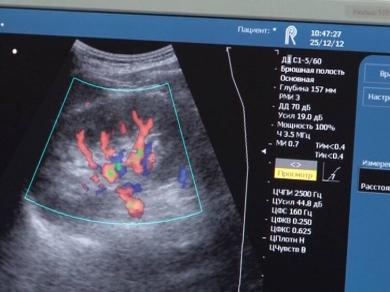

А цей ультразвуковий апарат також заміна попереднику випуску минулого сторіччя. Удосконалений і сучасно укомплектований. В "Обласному спецдиспансері радіаційного захисту населення", згідно його специфіки, він вкрай необхідний, зазначають медики. Крім того для диспансеру було придбано й інше устаткування, облаштувано і відремонтовано стоматкабінет. З обласного бюджету на це було виділено 4 мільйони гривень.

-Це і рентгенівський апарат, 2 ультразвукові апарати, стоматкабінет, виділено тут сьогодні фізіотерапевтичне обладнання. Два кардіографи і обладнання операційне. Нами розроблено проектно-кошторисну документацію для суттєвих змін в цій установі.